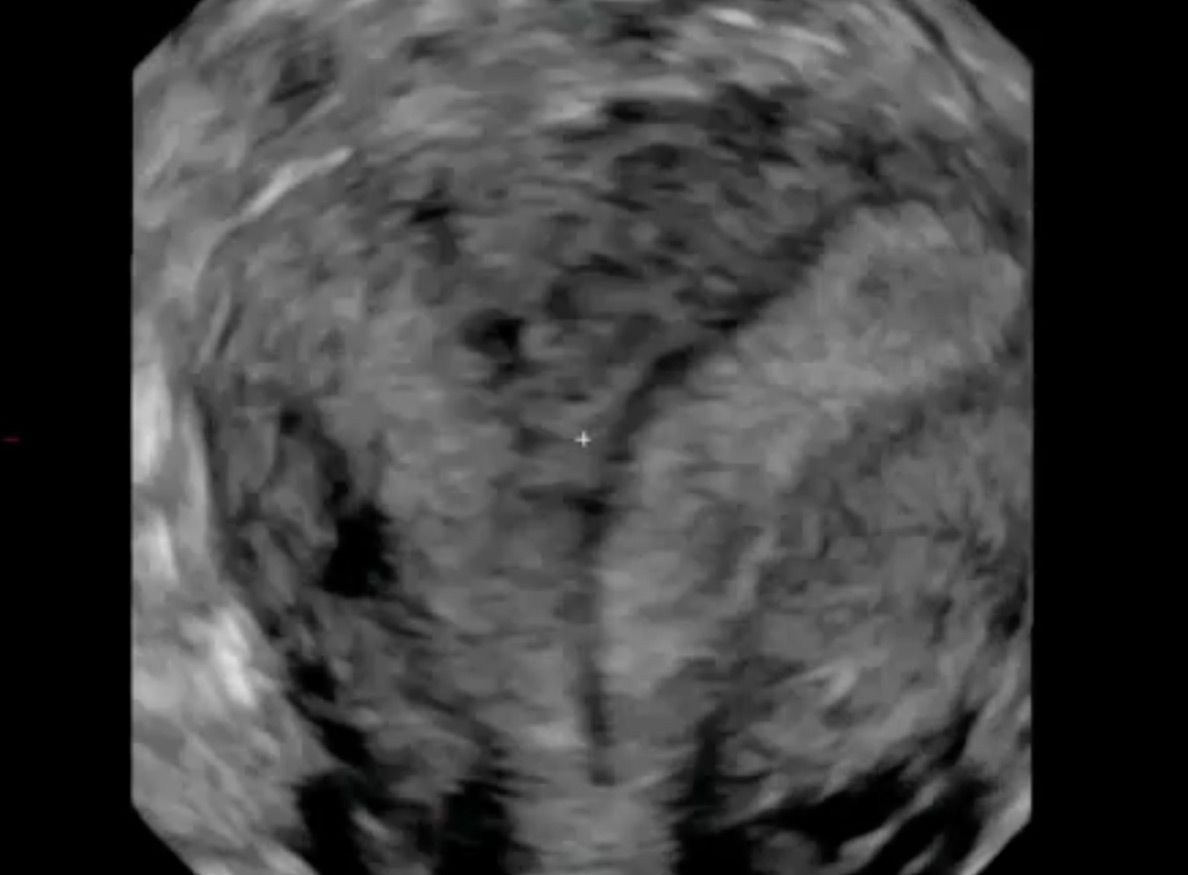

Uterus septiert

Die Universitätsfrauenklinik ist ein ausgewiesenes Zentrum für Pränataldiagnostik und Fehlbildungen des inneren Genitals. Diese bleiben lange symptomlos verborgen, können jedoch bei Eintritt der Pubertät, bei unerfülltem Kinderwunsch oder wiederholten Fehlgeburten in den Vordergrund treten. In vielen Fällen kann eine gezielte  operative Therapie die Beschwerden lösen bzw. die Schwangerschaftsraten verbessern.